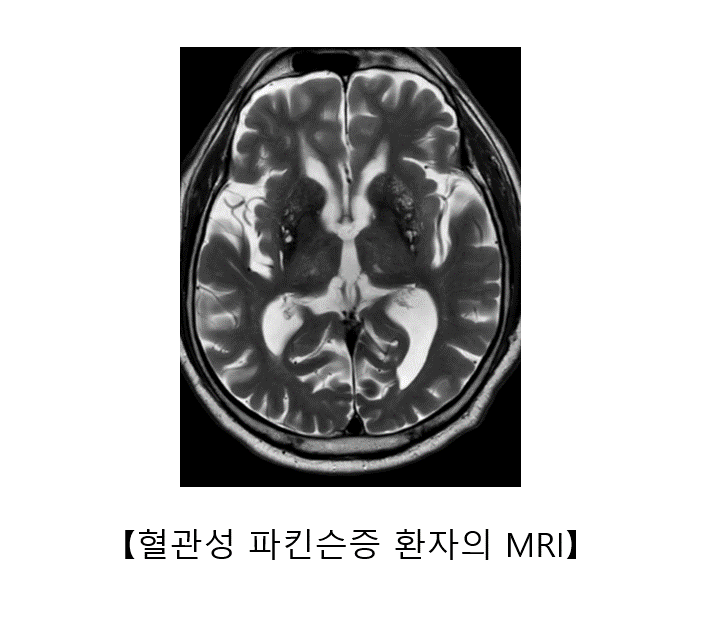

혈관성 파킨슨증은 뇌의 기저핵이나 피질하 백질에 분포하는 작은 혈관들의 장애로 발생합니다. 갑작스럽게 발생하는 일반적인 뇌경색 증상과는 달리, 발음 이상, 운동 완만, 보행 장애, 인지 기능의 저하 등의 증상이 서서히 진행할 수 있습니다. 이 중 가장 두드러진 증상은 보행 장애로, 종종걸음, 동결 보행 등의 모습을 보입니다. 배뇨 장애도 흔히 동반됩니다.

혈관성 파킨슨증은 뇌 자기공명영상에서 뇌의 기저핵과 뇌실 주변에 허혈성 병변이 동반된 경우에 의심할 수 있습니다. 혈관 질환이 더 진행되지 않도록 항혈소판제를 투여하거나, 고혈압, 당뇨, 고지혈증과 같은 혈관성 위험 인자를 철저하게 관리하는 것이 중요합니다. 혈관성 파킨슨증은 레보도파에는 거의 반응하지 않는 것으로 알려져 있습니다.